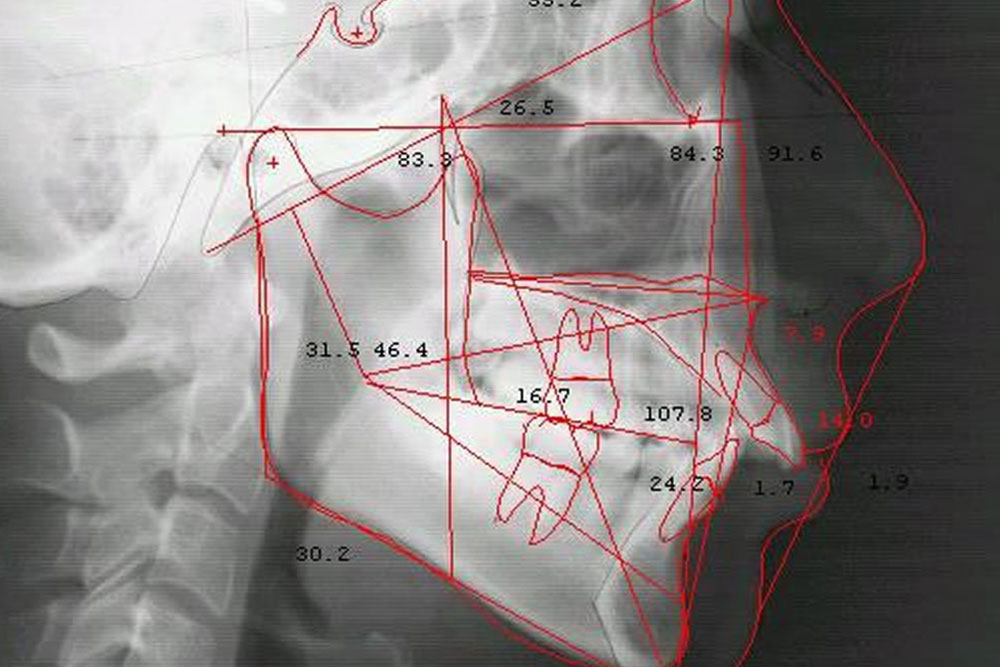

① 咬みあわせ精密診断

咬みあわせの治療を始める前に、虫歯や歯周病の検査を行います。その後、セファロレントゲン等の機器を使用し、現在の咬みあわせや顎関節や筋肉などの状態を診断します。また、必要に応じて口内の写真や姿勢なども撮影します。

セファロレントゲン

通常のレントゲンでは撮影が不可能なセファログラムが撮影可能な特殊なレントゲンです。矯正治療には必須と言われるほど重要で、顎・顔面・頭部を撮影し、トータル的な検査や分析を可能にします。規格が一定のため、治療前後の比較や小児矯正においてはお子様の発育を予想する事が可能です。